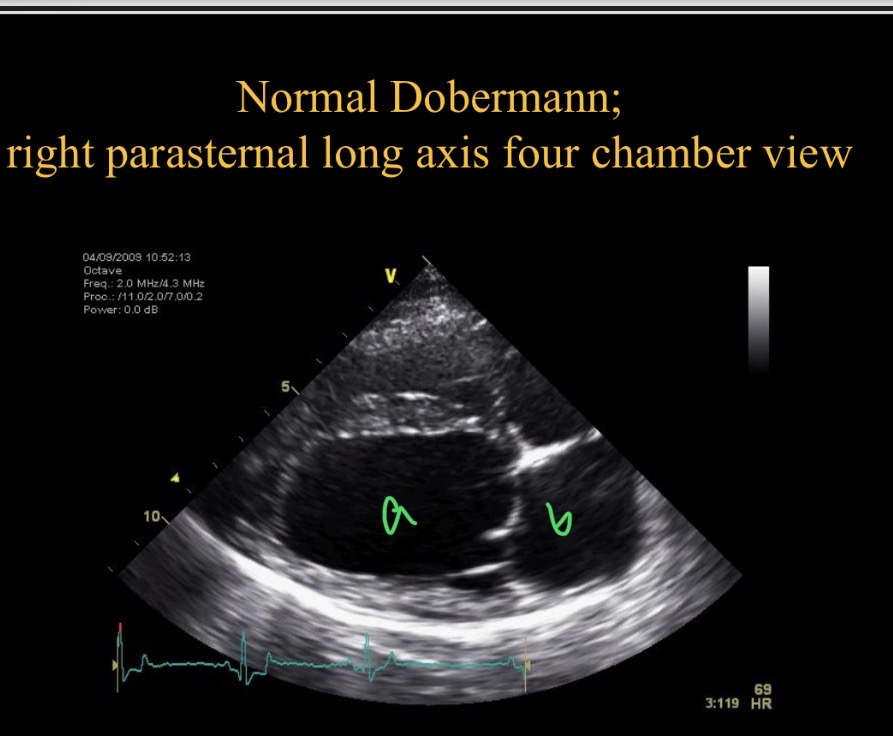

R para sternal long axis 4 chamber view

Types of views - RPS view which chamber is clostest to probe

RV

Which chamber is A

LV

Which chamber is B

LA